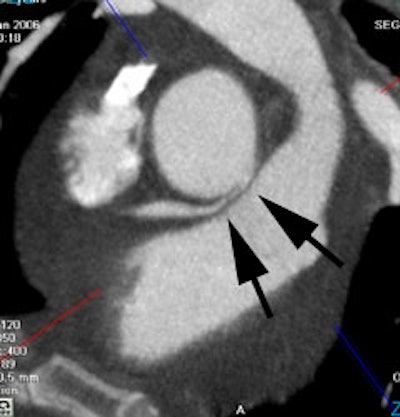

Anomalous RCA origin from the left coronary sinus: The patient below underwent coronary CT angiography to assess for coronary artery disease. The patient was found to have an anomalous RCA arising from the left sinus of valsalva. The vessel can be seen to course between the pulmonary trunk and aorta (black arrows) |

|